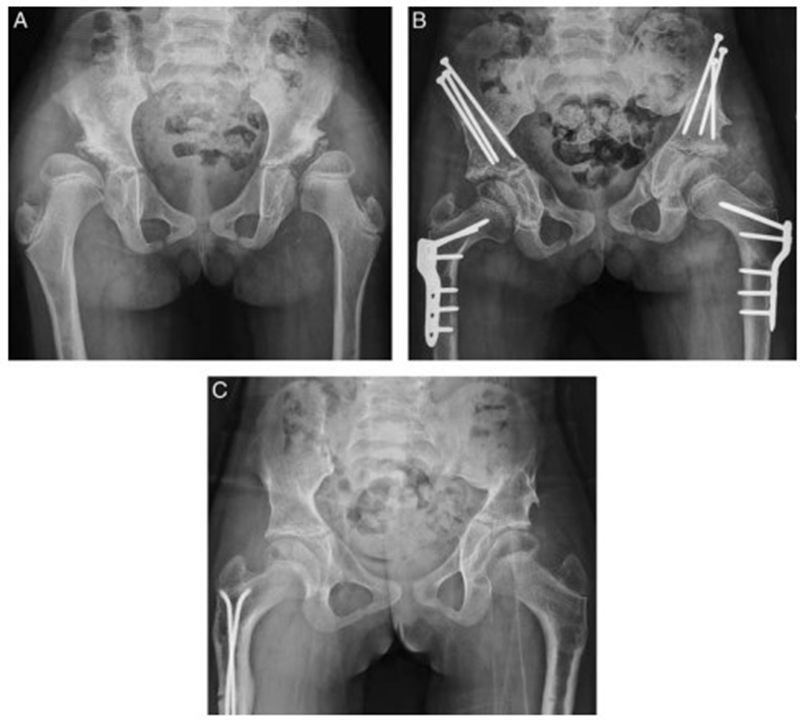

8岁患儿,双侧DDH,外院行切开复位手术后,残留畸形,经JST微创骨盆三联截骨后,末次随访提示髋关节包容好